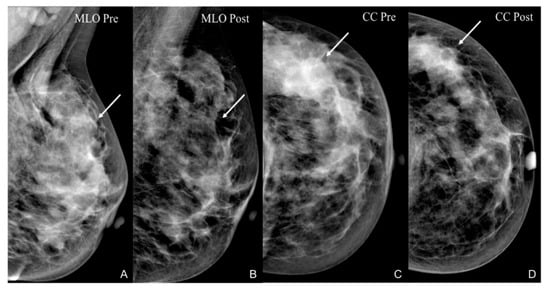

- Park, J.; Chae, E.Y.; Cha, J.H.; Shin, H.J.; Choi, W.J.; Choi, Y.-W.; Kim, H.H. Comparison of mammography, digital breast tomosynthesis, automated breast ultrasound, magnetic resonance imaging in evaluation of residual tumor after neoadjuvant chemotherapy. Eur. J. Radiol. 2018, 108, 261–268. [Google Scholar] [CrossRef]

- Dialani, V.; Chadashvili, T.; Slanetz, P.J. Role of Imaging in Neoadjuvant Therapy for Breast Cancer. Ann. Surg. Oncol. 2015, 22, 1416–1424. [Google Scholar] [CrossRef] [PubMed]